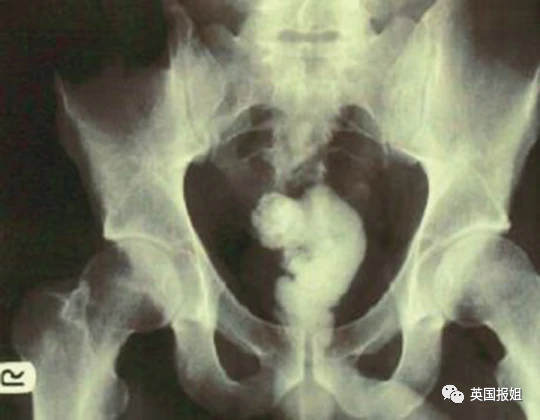

左:茄子 右上:铝罐 右下:咖啡罐

可以看出这些患者对于球形的、柱状的和长条形的物体有一些奇怪的执念。但有些患者也会突破这些形状的桎梏,寻找更多样的物品嵌入体内。

当固体已经满足不了他们的时候,还有人毅然决然选择了流体:这名美国27岁男子用胶枪将融化的黏合剂给自己灌肠,黏合剂进入体内后迅速凝固,坚若磐石: